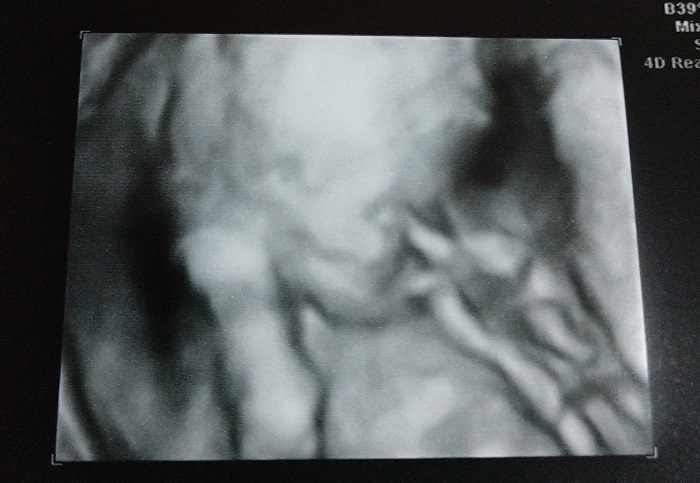

As we watched the screen, the baby was moving arms and legs. The hand was up near the face, and the tech said that there may be some thumb sucking going on. For a short time, it did not look like the baby was going to cooperate and let us see anything. Finally, the tech was able to find the baby’s butt. At this angle, we could finally see…

Our baby is a girl! I do not have the ability to put into words the feelings I experienced at that moment. I remember looking back at Sam and seeing her face. Seeing her smile made the emotions even more overwhelming. Fighting back tears, I turned back to the screen to watch as the tech pointed out features on the ultrasound.

The tech could go from the regular ultrasound to the 3D pictures, and it was very cool to see. We will be going back later in the pregnancy to see more. They told us that at this young, it is a bit hard to see and that there were things that were still developing. This is a shot of our baby with her hand up near her face. It was very cool to see and I am excited to see her again in a few months.